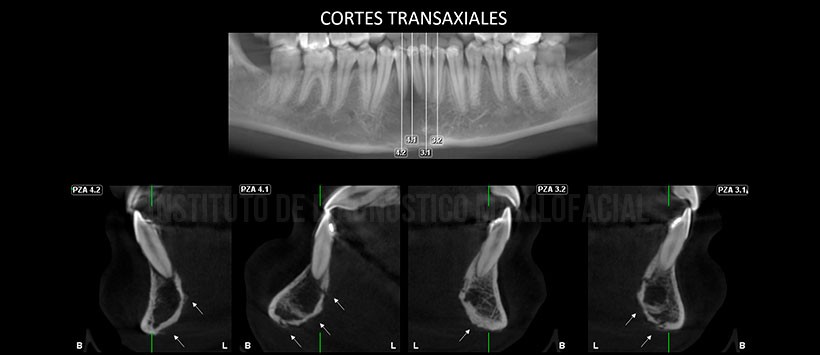

En la evaluación mediante tomografía volumétrica de haz cónico, evidenciamos la presencia de un proceso osteolítico en la zona previamente mencionada, comprometiendo ambas tablas óseas y  borramiento de cortical de las piezas 41 y 41. Así mismo se evidencia una reacción periostal a nivel de la basal mandibular y tabla ósea lingual, alterando su propia morfología en zonas de las piezas 31, 32, 41 y 42. (Figura 3 y Figura 4)